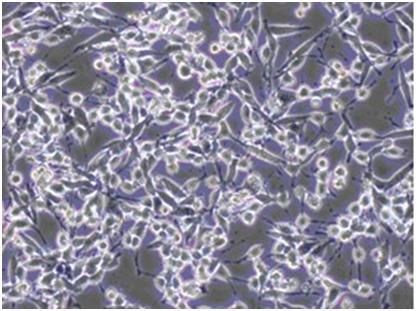

脐带间充质干细胞

近年来,间充质干细胞在临床应用中的广阔前景日益凸显。新生儿的脐带组织作为间充质干细胞的理想来源,具有取材方便,无道德伦理争议,可获取的细胞数量多、增殖能力强、免疫调节作用大等优势,极其适合用于临床研究和应用。